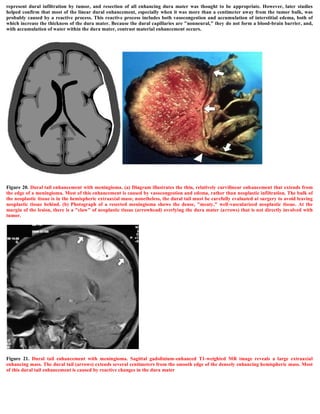

 The dural tail or "dural flair"

The dural tail is a curvilinear region of dural enhancement adjacent to the bulky hemispheric tumor. The finding was originally thought to

represent dural infiltration by tumor, and resection of all enhancing dura mater was thought to be appropriate. However, later studies

helped confirm that most of the linear dural enhancement, especially when it was more than a centimeter away from the tumor bulk, was

probably caused by a reactive process. This reactive process includes both vasocongestion and accumulation of interstitial edema, both of

which increase the thickness of the dura mater. Because the dural capillaries are "nonneural," they do not form a blood-brain barrier, and,

with accumulation of water within the dura mater, contrast material enhancement occurs.

Figure 21. Dural tail enhancement with meningioma. Sagittal gadolinium-enhanced T1-weighted MR image reveals a large extraaxial

enhancing mass. The dural tail (arrows) extends several centimeters from the smooth edge of the densely enhancing hemispheric mass. Most

of this dural tail enhancement is caused by reactive changes in the dura mater

Figure 28. The characteristic meningeal tail on the contrast enhanced T1 MRI images

Figure 27. The characteristic meningeal tail on the contrast enhanced T1 MRI images